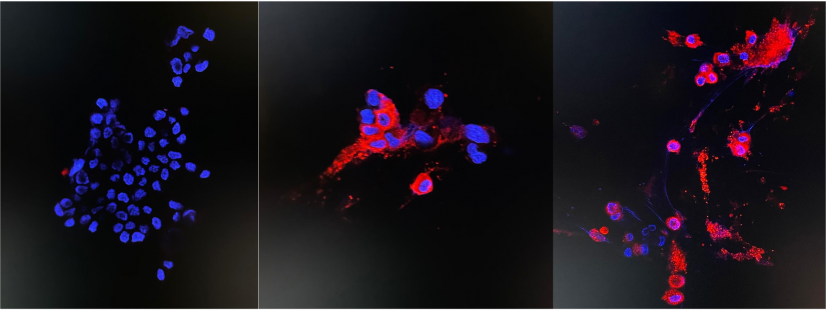

Immunofluorescence staining of uninfected and infected Vero E6 cells

left: Uninfected sample (the negative control)

middle: 24 hours post infection

right: 48 hours post infection (see red fluorescent cytoplasmic antigen staining under confocal microscopy)

Various markers show that the isolation and culture of the virus was successful. Cytopathic effects with cell rounding and shrinking started to appear at 24 hours and were complete in 48 hours. Immunofluorescent staining of the infected cell line showed abundant nucleocapsid protein expression.